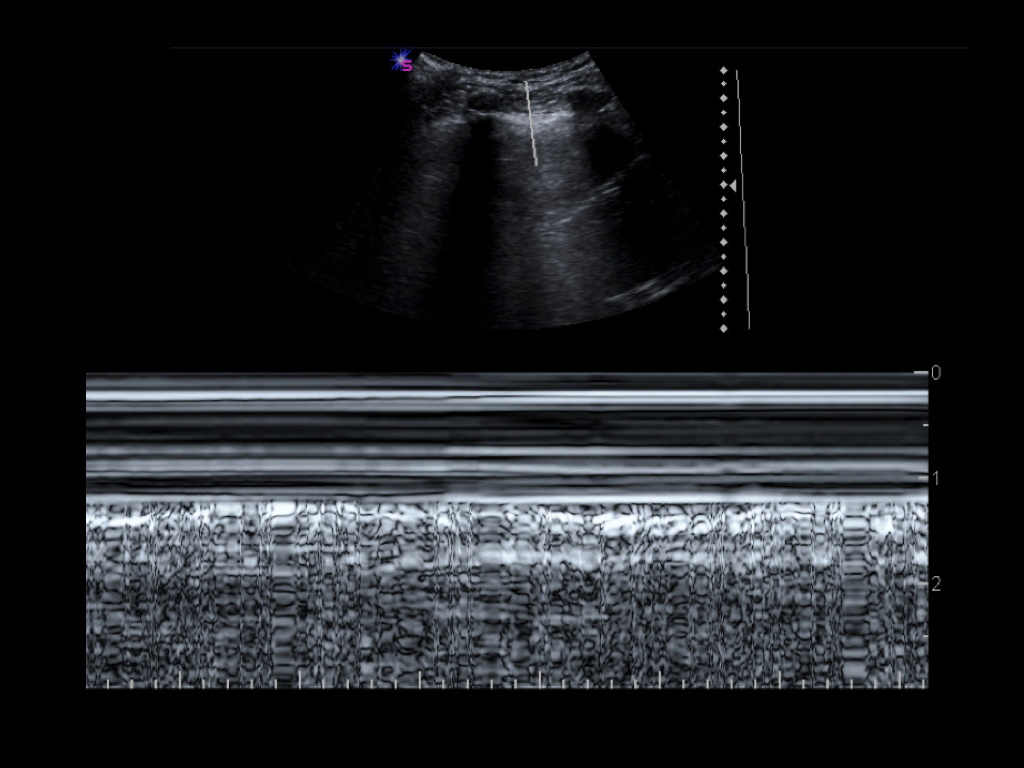

- Im M-Mode: ein Strahl wird durch das subkutane Gewebe, die Interkostalmuskulatur, Pleura und Lunge gelegt. Bei normalen Verhältnissen entsteht unterhalb der Pleuralinie ein granuliertes Muster, während im Bereich der Cutis, Subcutis und Interkostalmuskulatur ein lineares Muster entsteht („Seashore-Sign“). Bei Vorliegen eines Pneumothorax ist aufgrund der fehlenden Bewegung im Bereich der Pleuralinie ein durchgehend lineares Muster zu beobachten („Barcode-Sign“).